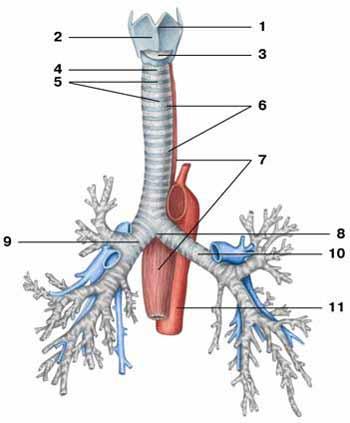

C-Rings (=tracheal cartilage)

Epiglottis

Esophagus

Larynx

Left/right primary bronchus/bronchi

left/right pulmonary artery/vein

Secondary bronchi

Trachae